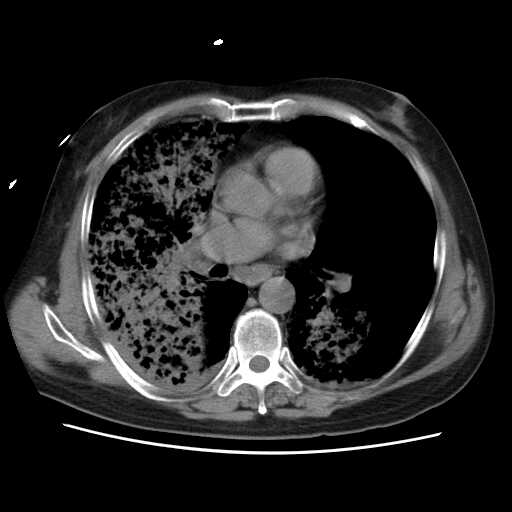

病变从8.11-8.17明显改变,增多,以蜂窝状改变为主,类蜂窝肺,似弥漫性肺泡癌,但是病变进展太快,不符合弥漫性细支气管肺泡癌。因此考虑为特殊微生物感染,多以霉菌类常见,建议细菌微生物学检查。

追踪结果,该病人已于2008.8.18日经抢救无效死亡.死于呼吸衰竭.具体病因不明,未作死体解剖.

疑点一:起病急,来势汹.

疑点二:影象表现怪异,大片阴影内见多发筛孔征,如何解释.

结合临床慢支炎肺气肿,肺心病病史,三次胸片观察可见病情发展变化迅速,病情凶险,考虑多重感染伴ards.